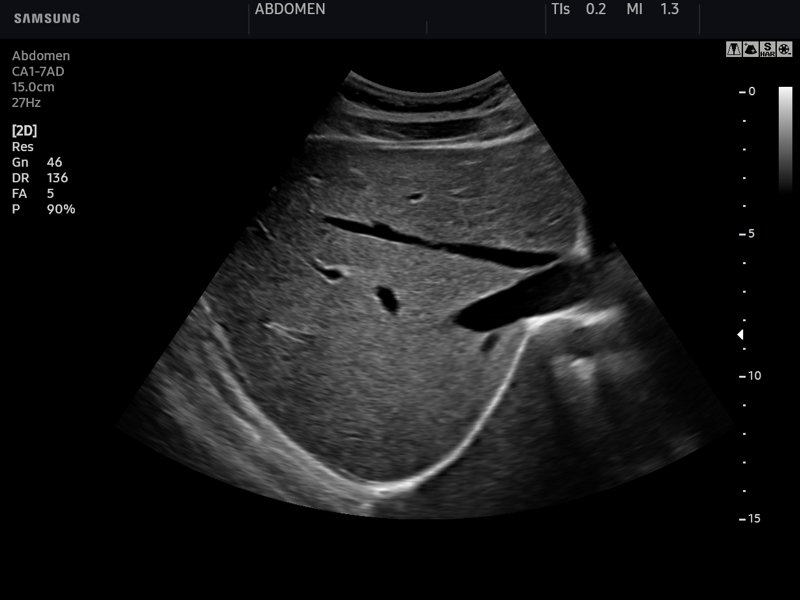

Печень, B-режим (эхограмма №763)

Изображение получено с помощью УЗ сканера HS50 (есть в продаже).